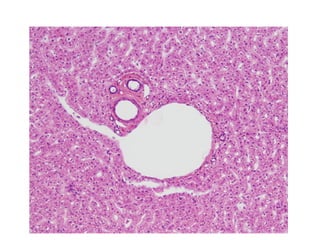

Liver Lobules

• Each lobe is divided by CT into ~100,000 liver

lobules – basic functional units of the liver

- hepatocytes form a series of plates (like spokes around

a wheel), each plate is only 1 cell thick

- exposed heptocyte surfaces are covered with short

microvilli

- sinusoids between adjacent plates empty into the central

vein

- sinusoidal lining includes a large number of Kupffer

(stellate reticuloendothelial) cells, part of the monocytemacrophage system

- Kupffer cells engulf pathogens, cell debris, damaged

blood cells and also any heavy metals (tin and mercury)

• Blood enters liver sinusoids from small branches

- 6 portal areas, or hepatic triads, one at each of the 6

corners of the lobule; contains 3 structures:

1) a branch of the hepatic portal vein

2) a branch of the hepatic artery proper

3) a small branch of the bile duct

- as blood flows through the sinusoids, hepatocytes absorb

and secrete materials into the bloodstream

- blood then leaves the sinusoids and enters the central

vein of the lobule

- central veins merge to form the hepatic veins that empty

into the inferior vena cava

Liver Histology

Figure 25.21